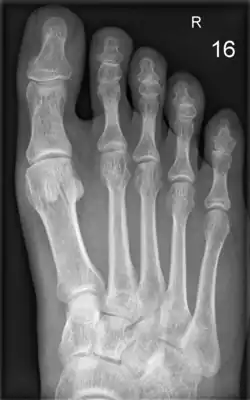

Röntgenbild der Fußknochen des Menschen

Die Zehenknochen (Ossa digiti oder Ossa digitorum pedis) ähneln im Aufbau den Fingerknochen. Die große Zehe besitzt zwei Glieder, alle übrigen Zehen sind dreigliedrig. Die Glieder werden in Grundglied (Phalanx proximalis), Mittelglied (Phalanx media) und Endglied (Phalanx distalis oder Phalanx unguicularis) unterteilt. Bei Huftieren werden sie als Fessel-, Kron- und Hufbein bezeichnet. An den Zehenknochen lassen sich die Basis, der Körper und der Kopf unterscheiden.

Die Gelenke zwischen Mittelfußknochen und Grundgliedern werden als Zehengrundgelenke (Metatarsophalangealgelenke) bezeichnet. Das Gelenk zwischen Grund- und Mittelglied trägt die Bezeichnung Mittelgelenk oder proximales Interphalangealgelenk (PIP). Zwischen dem Mittel- und dem Endglied befindet sich das Endgelenk (distales Interphalangealgelenk, DIP).